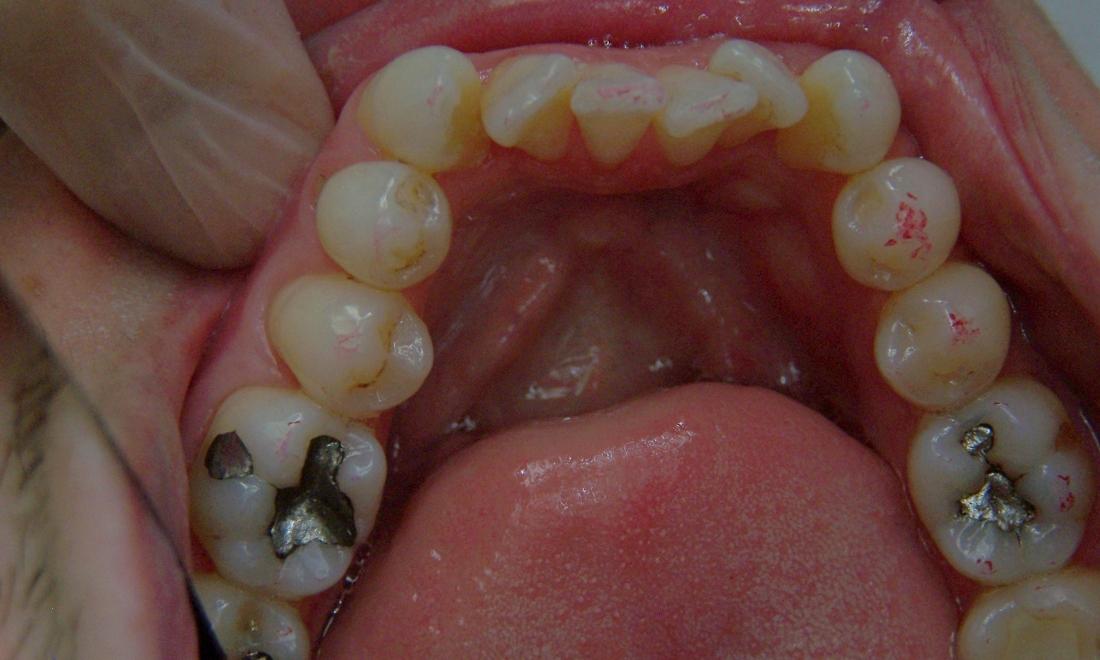

This patient's "before" photo shows their crooked, misaligned teeth and the gaps between the top and bottom rows of their smile. However, by using adult braces, we pulled their teeth into alignment and produced a straighter, healthier smile.